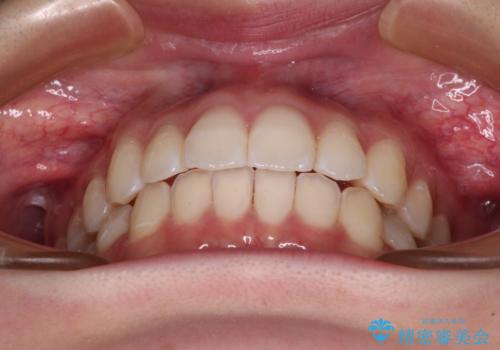

治療途中、出産や転居があり、2年ほど治療期間が長くなってしまいましたが、前歯の歯並びや飛び出した感覚を無事に改善させることができました。

インビザラインによる上下歯列の側方拡大と後方移動、必要に応じてIPR(歯と歯の間を削る)によりスペースの獲得により歯列を整えることとしました。